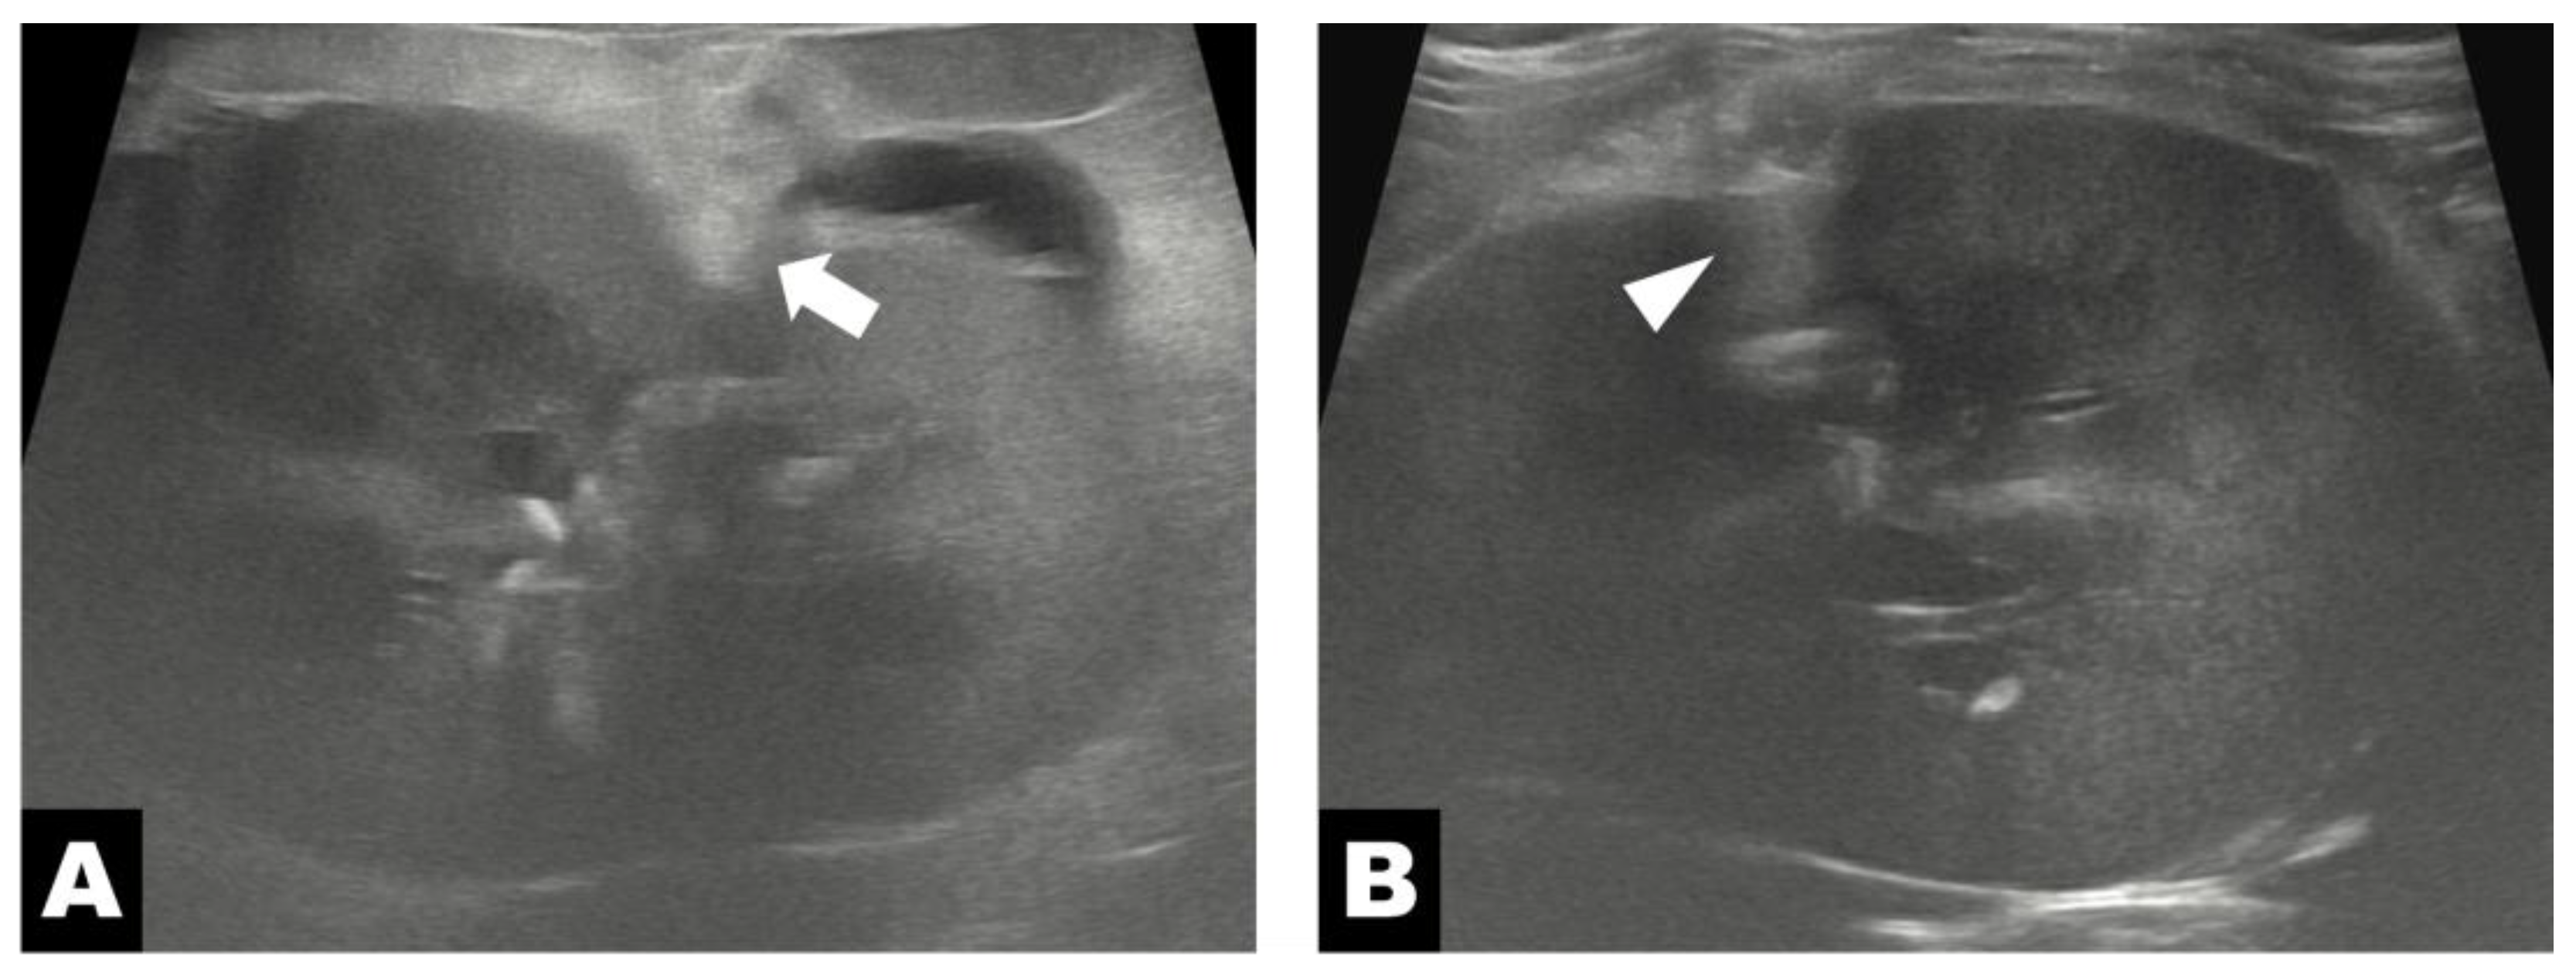

Abdominal ultrasonography, performed using a diagnostic ultrasound system (ARIETTA 70; Hitachi-Aloka, Tokyo, Japan) equipped with a high-frequency linear transducer (2–12 MHz), revealed extensive subcapsular fluid surrounding the entire left kidney between the renal parenchyma and capsule, with thinning of the renal cortex due to compressive effects (Figure 1A). As the cat had a solitary kidney, intrarenal regional measurements were compared. The preoperative renal volume was 34.08 cm3. At regions distant from the diverticular lesion, cortical and medullary thicknesses were 7.3 mm and 12.2 mm, respectively, with a medulla-to-cortex ratio of 1.67. In contrast, measurements obtained adjacent to the diverticular lesion demonstrated marked parenchymal thinning, with cortical thickness of 3.3 mm and medullary thickness of 6.9 mm, corresponding to an increased medulla-to-cortex ratio of 2.09. In addition, a narrow anechoic channel connecting the renal pelvis to the adjacent subcapsular space was identified, suggesting the presence of an open tract rather than an isolated closed cystic lesion (Figure 1B).

Figure 1. Preoperative ultrasonography of the left kidney. (A) Perinephric fluid accumulation within the pseudocyst wall (white arrow) around the kidney. (B) The diverticulum (asterisk) appears as cystic cavities near the renal pelvis (white hollow arrow).